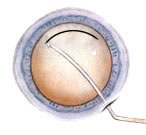

CATARACTOUS LENS BEING BROKEN BY PHACO NEEDLE THROUGH

1 MM to 2.8 MM IN INCISION

In this surgery the cataractous lens is broken down into small pieces with the help of ultra sound energy and sucked out. The operation is done through a < 1 mm to 2.8 mm small tunnel incision so that after operation no stitches are required because incision is self sealing. Intra ocular lens is also implanted through the same incision. The foldable lenses are used these days. These lenses get folded and are loaded in a plastic injection. The lens is then injected into the eye through the small incision made for surgery.